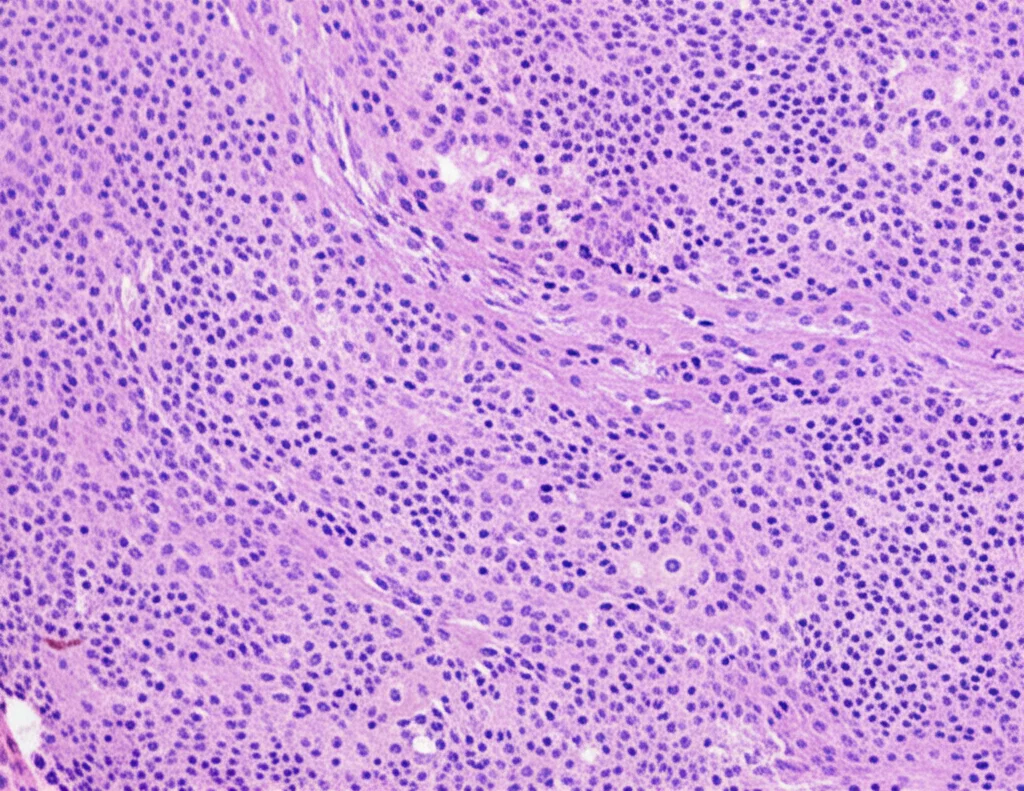

Dopo vari accertamenti, una biopsia di un linfonodo ha rivelato una condizione chiamata trasformazione progressiva dei centri germinativi (PTGC) associata a un aumento dell’espressione di IgG4. Questa combinazione ha portato alla diagnosi di una forma particolare di malattia correlata alle IgG4 (IgG4-RD). Le malattie IgG4-RD sono un gruppo di disturbi fibroinfiammatori che possono colpire diversi organi, caratterizzati dall’accumulo di plasmacellule che producono un tipo specifico di anticorpi, le IgG4.